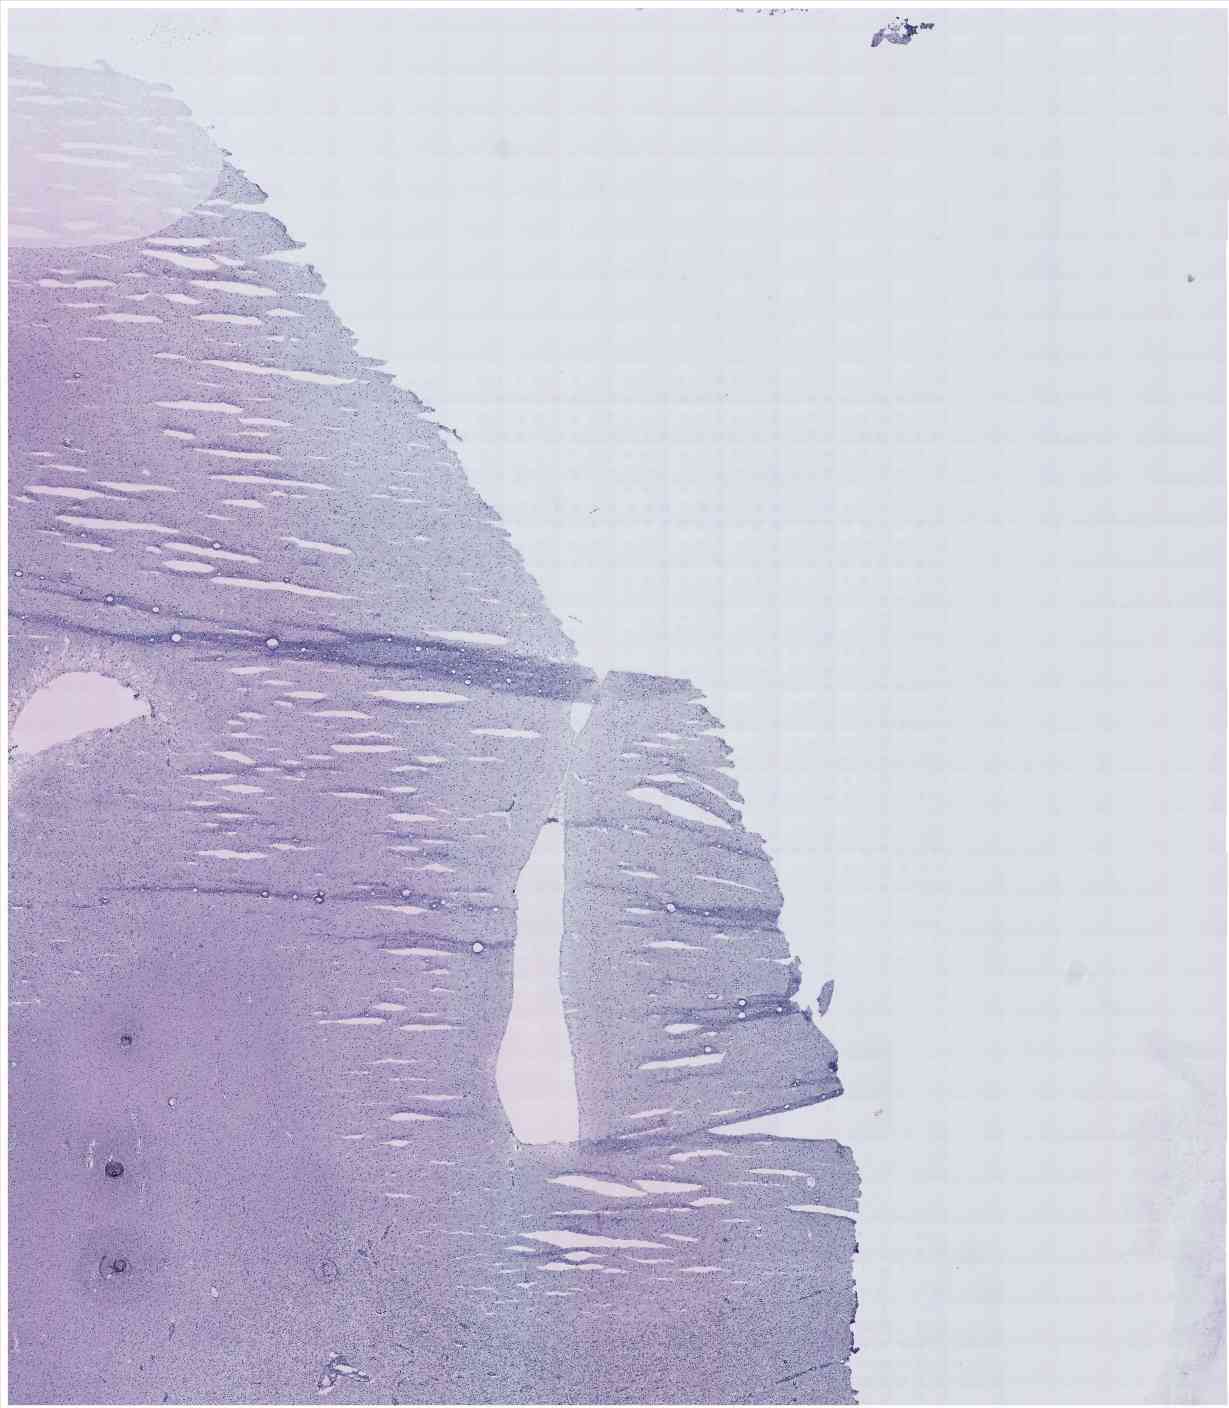

Chip 037 Well C2